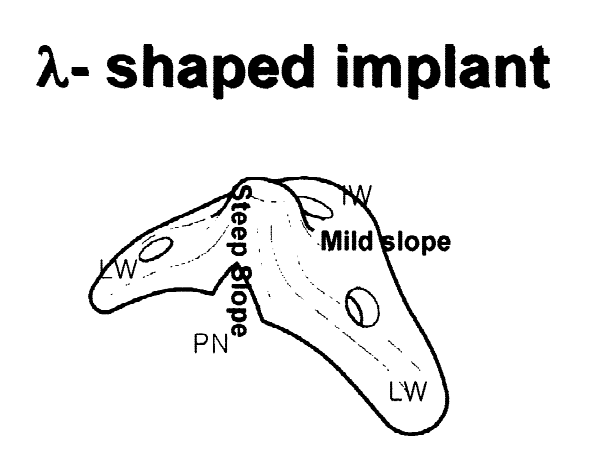

- Implant desgined to mimic the pointiness of the ANS. The implant projecfts the ANS forwards along with the nose base.

- Can be superior to grafting as it provides better contour and results are more predictable.

- This can increase the projection of the septum by 2 mm max according to giant.

- Recommended to be placed during rhinoplasty. Can be placed during bimax as long as it doesnt block the plates, but this is not recommended and can yield unfavorable results.